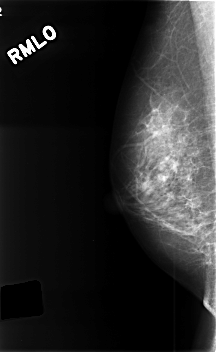

C_0385_1.RIGHT_MLO

RIGHT_MLO LINES 4576 PIXELS_PER_LINE 2808 BITS_PER_PIXEL 12 RESOLUTION 50 NON_OVERLAY